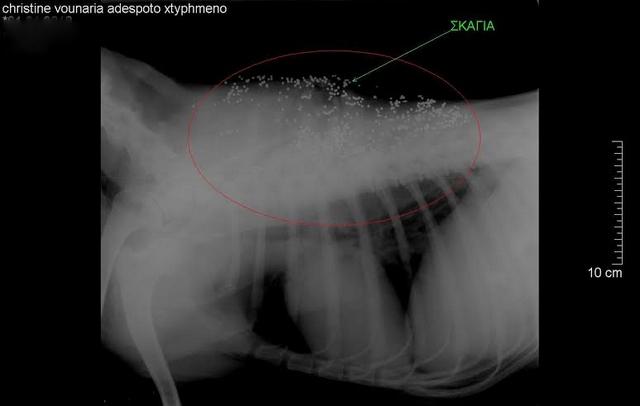

Οι κτηνίατροι που εξέτασαν και εγχείρισαν το άτυχο ζώο διέγνωσαν ότι είχε πυροβοληθεί εξ επαφής και τα σκάγια είχαν πάει σε όλο του το σώμα, ενώ έχει υποστεί πολλά κατάγματα.